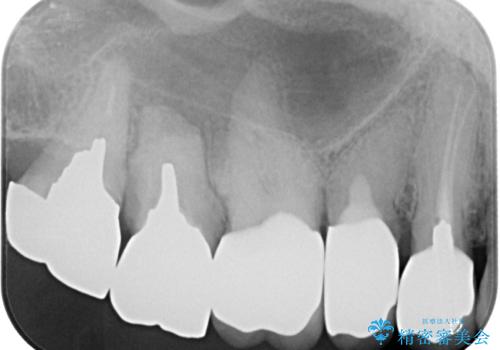

奥の銀歯の幅が大きかったこともあり、細長いクラウンの見た目は大きく改善することができました。

今後は他の銀歯の治療を進めていく計画です。